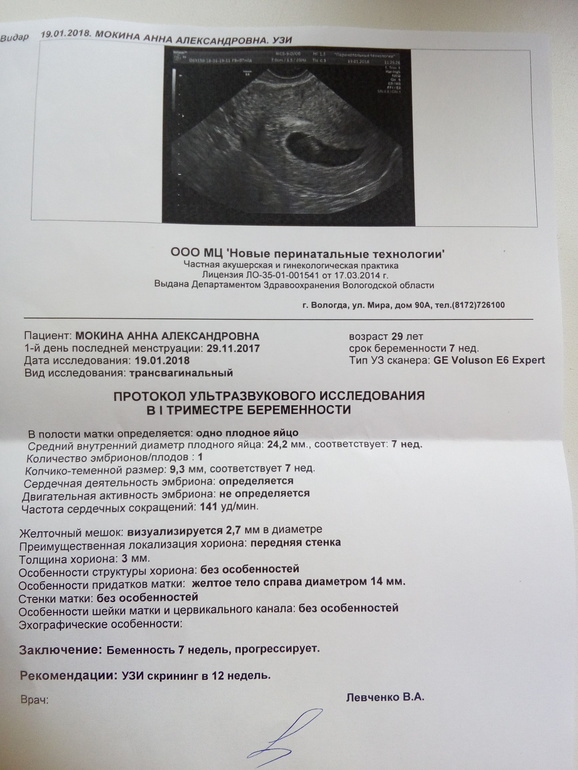

Развитие эмбриона на 8 неделе беременности